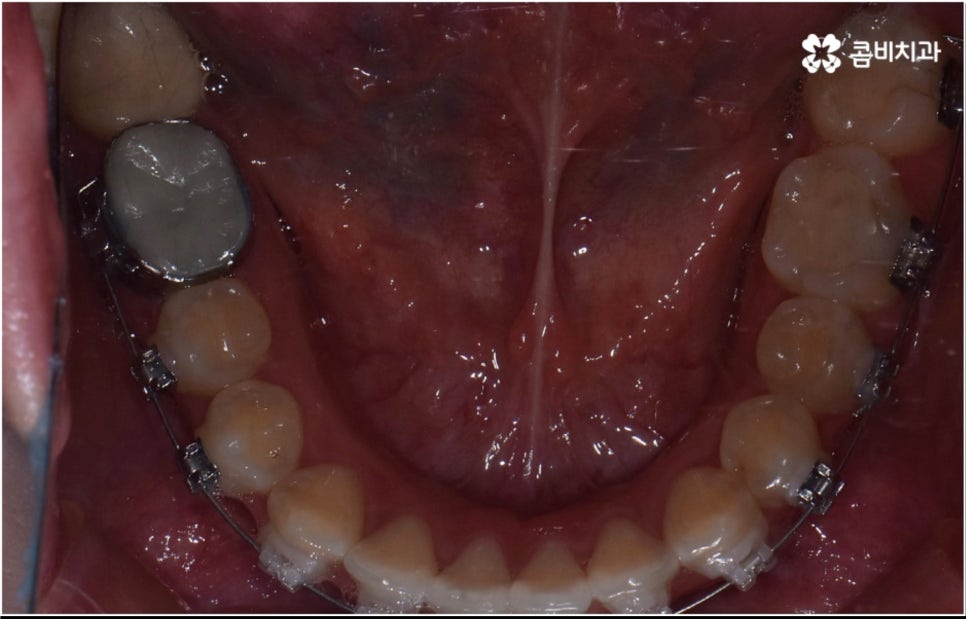

3D CT 등 정밀 검진 기계를 통해 꼼꼼하게 검진을 한 후 환자분들의 부정교합의 종류 및 정도 등에 따라 각자에게 맞는 교정 치료 계획을 수립하게 되는데, 내부 공간이 얼마나 있는지에 따라 발치가 필요한지 아닌지 여부도 달라지고 또 같은 부정교합이라고 해도 사람마다 잇몸 건강이나 치근 상태 등에 따라 잇몸뼈가 벌어지면서 치아가 이동하는 속도, 치아가 자리잡는 양상 등도 모두 달라지기 때문에 성인 치아교정 기간 총 소요 시간은 모두 달라질 수 밖에 없을 거예요.

하지만 부정교합의 정도가 심하거나 골격적 문제를 바로잡아 주어야 하는 경우는 전체 교정을 진행해야 하기 때문에 (환자분들마다 다르지만) 평균적으로 18~36개월 정도의 성인 치아교정 기간 이 소요되며, 중장년 성인분들 중에 잇몸 질환 등으로 구강 건강이 약해져 있는 분들의 경우에는 더욱 환자분들의 상황에 맞게 필요한 치료를 병행하면서 무리하지 않은 진행을 해야 하기 때문에 전체 기간이 좀 더 늘어날 수 있어요.

치아 색상의 세라믹 브라켓을 이용하는 장치들은 예전 메탈 장치 보다 심미성이 훨씬 보완되었으며, 치아 뒤쪽에 장치를 부착하여 아예 눈에 띄지 않는 설측교정장치나 언뜻 보면 티가 잘 나지 않는 얇고 투명한 특수 강화 플라스틱을 이용하는 투명교정장치를 이용하면 교정을 하고 있다고 본인이 말을 하지 않으면 잘 모를 정도로 심미성이 뛰어나기 때문에 각 장치들의 소재와 특성, 장단점에 대해서 잘 알아보고 신중한 선택을 하는 것이 중요하다고 할 수 있어요.